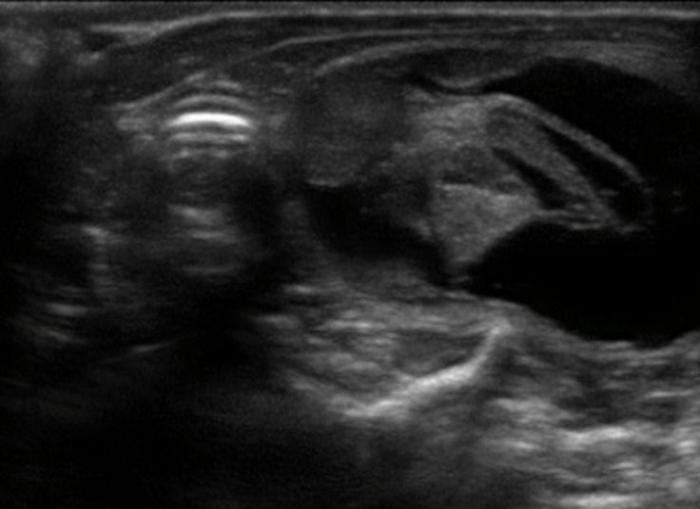

La glándula tiroides en perros y gatos está constituida por dos lóbulos situados a ambos lados de la tráquea cervical, con disposición longitudinal y una forma fusiforme o alargada que se extiende desde el cartílago cricoides hasta la entrada torácica superior2. En condiciones normales, cada lóbulo presenta contornos bien definidos, cápsula hiperecogénica delgada y parénquima homogéneo, con una ecogenicidad generalmente igual o ligeramente superior al músculo esternohioideo adyacente3,8. En la imagen transversal, los lóbulos suelen adoptar una configuración oval o ligeramente triangular (Figura 1); en longitudinal, se observa una forma alargada con extremos redondeados y orientación paralela a los vasos carotídeos y la tráquea1 (Figura 2).

La localización anatómica superficial de la glándula, junto con su estructura relativamente uniforme, facilita su identificación mediante ultrasonografía de alta resolución. Entre los reparos anatómicos más importantes para su localización se encuentran las arterias carótidas comunes (laterales), la tráquea (medial) y los músculos esternotiroideos (ventrales), mientras que el esófago puede constituir una referencia dorsal del lóbulo izquierdo15 (Figuras 3 y 4).